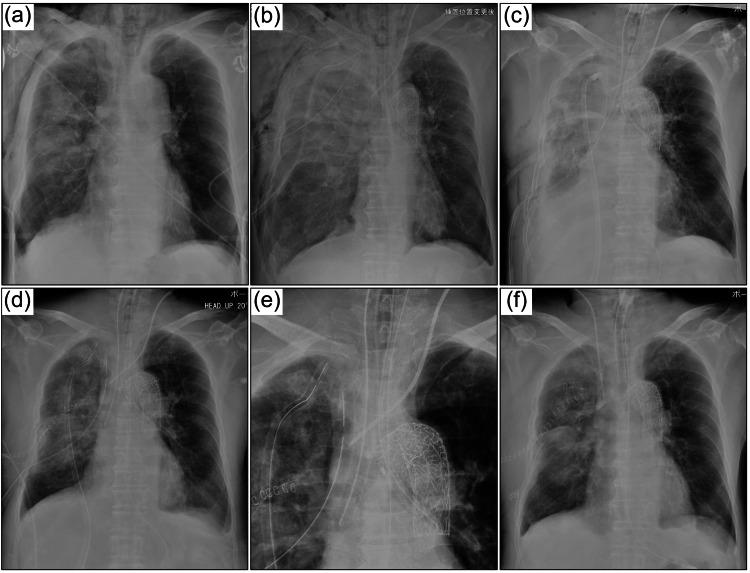

A 72-year-old man presented with severe pulmonary contusions and multiple traumas, including aortic injury, pelvic fracture, and renal injury. The patient required multidisciplinary treatment, including transcatheter arterial embolization, thoracic endovascular aortic repair, right lung upper lobe partial resection, and massive transfusion. During the initial treatment, the patient experienced respiratory failure due to endotracheal bleeding, and we attempted isolated lung ventilation with a 37 Fr double-lumen endotracheal intubation tube. Although drainage by suction and protection of the healthy lung was vital, the patient was unable to maintain ventilation volume because of poor drainage. Additionally, the respiratory status deteriorated. To resolve the situation, a tracheotomy was performed and two endotracheal intubation tubes (6.0 mm inner diameter, and 9.0 mm outer diameter) were inserted through a large U-shaped tracheal hole 18 hours after admission. The respiratory status of the patient gradually improved after the procedure. There were two advantages of this method of respiratory management. Firstly, each of the two endotracheal tubes had a separate cuff, allowing more reliable separation of the healthy lung from the injured lung. Secondly, bronchoscopes of sufficient diameter (4.9 mm outer diameter ) were used bilaterally, allowing sufficient drainage of viscous airway secretions mixed with hematoma and improving atelectasis. Although venovenous extracorporeal membrane oxygenation is a crucial support tool when the respiratory status deteriorates due to severe pulmonary contusions, our method of airway management may be attempted in patients with multiple traumatic injuries with coagulopathy.

一名72岁男性因严重肺挫伤及多处创伤入院,包括主动脉损伤、骨盆骨折和肾损伤。患者需要多学科治疗,包括经导管动脉栓塞术、胸主动脉腔内修复术、右肺上叶部分切除术及大量输血。在初始治疗期间,患者因气管内出血出现呼吸衰竭,我们尝试使用37 Fr双腔气管插管进行单肺通气。尽管通过吸引进行引流及保护健侧肺至关重要,但由于引流不畅,患者无法维持通气量。此外,呼吸状况恶化。为解决这一情况,入院18小时后行气管切开术,并通过一个大的U形气管造口插入两根气管插管(内径6.0 mm,外径9.0 mm)。术后患者的呼吸状况逐渐改善。这种呼吸管理方法有两个优点。首先,两根气管插管各有一个单独的套囊,能更可靠地将健侧肺与损伤肺分隔开。其次,双侧使用了足够直径(外径4.9 mm)的支气管镜,能充分引流混有血肿的黏稠气道分泌物并改善肺不张。尽管当因严重肺挫伤导致呼吸状况恶化时,静脉-静脉体外膜肺氧合是一种关键的支持工具,但对于合并凝血病的多发创伤患者,可尝试我们的气道管理方法。